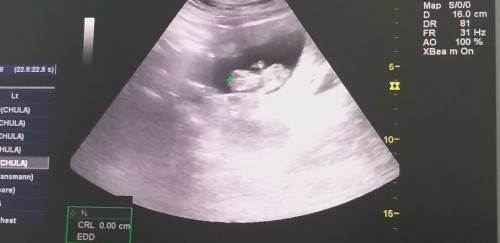

ตอนนี้ 13 วีค 2 วันแล้ว รู้สึกถึงว่าตัวน้อยของแม่ตอดแรงดี สนุก รู้สึกว่าทำไมดิ้นแรงกว่าท้อง 1 และ 2 สะอีก